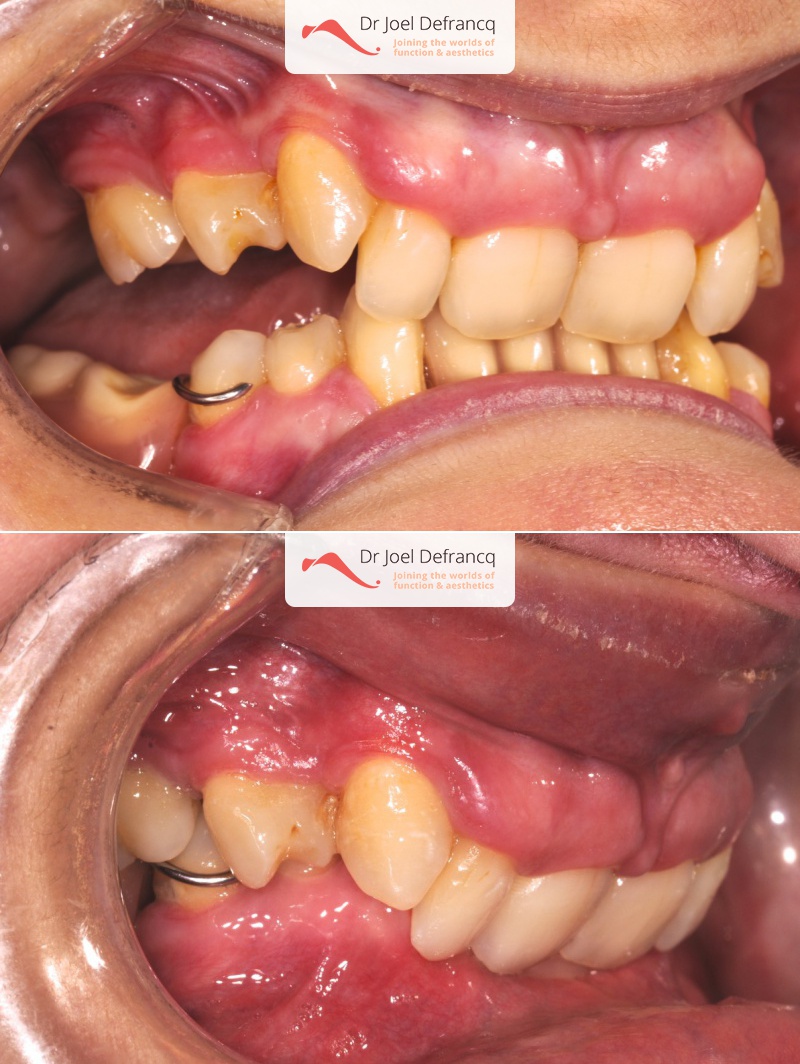

Balera: Extreme deep bite - implants

Diagnose van het gezicht

- Te kleine onderkaak (Overbeet)

Dentale diagnose

- Klasse II divisie 2